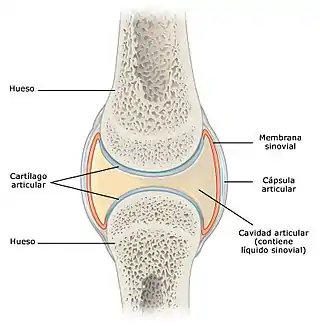

Ilustración de una articulación sinovial (diartrosis). | ||

Los huesos se enlazan mediante articulaciones que permiten el movimiento, existen diferentes tipos de articulaciones, pero una de las más importantes son las articulaciones sinoviales, representada entre otras por la cadera, rodilla, hombro y articulaciones interfalángicas de manos y pies. Tienen gran movilidad y están formadas por una cavidad llena de líquido sinovial y tapizada por la membrana sinovial. Los extremos de los huesos que la forman están recubiertos por cartílago articular. Todo el conjunto se refuerza exteriormente mediante una cápsula articular fibrosa que le da mayor estabilidad.[1][2]

Líquido sinovial

El líquido sinovial se encuentra en pequeñas cantidades en el interior de la cápsula articular y baña las superficies que forman la articulación. Tiene la función de nutrir y lubricar el cartílago, disminuyendo el roce de las superficies articulares, facilitando de esta forma el movimiento. Es producido por la membrana sinovial y tiene un alto contenido en ácido hialurónico.[3]

Membrana sinovial

Tapiza la superficie interna de la articulación. Forma numerosos pliegues y vellosidades, por lo que su superficie extendida es muy grande. Contiene varios tipos de células, los sinovocitos de tipo A, células similares a los macrófagos que limpian los restos metabólicos presentes en la articulación y los sinovocitos de tipo B que sintetizan ácido hialurónico, mucina que proporciona al líquido sinovial viscosidad y propiedades lubricantes.[4]

Cavidad articular

Corresponde al espacio que se interpone entre las superficies articulares de los huesos. Está lleno de líquido sinovial y rodeado por la membrana sinovial.

Cartílago articular

Desempeña un papel muy importante en las articulaciones sinoviales como la rodilla y el hombro, está constituido por cartílago hialino y recubre la superficie de los huesos, siendo su espesor entre 2 y 4 mm. Tiene la función de transmitir y amortiguar las cargas y proporcionar una superficie adecuada para el deslizamiento de las superficies articulares. No tiene vasos sanguíneos propios, por lo que las sustancias nutritivas le llegan a través del líquido sinovial. La capacidad de regeneración si sufre lesiones o desgaste por sobrecarga es escasa.[5] Está compuesto por células especiales llamadas condrocitos rodeados de matriz extracelular. La matriz extracelular está formada por agua (65-80 %), colágeno (10-20 %) y proteoglicanos (10-15 %) que le otorga resistencia a las fuerzas de compresión. Los condrocitos son las encargadas de producir los componentes estructurales que forman el cartílago.[5][6]

Hueso subcondral

Es la parte del hueso que se encuentra adyacente al cartílago articular.

Cápsula articular

La cápsula articular es una estructura formada por tejido conectivo denso que rodea la articulación y le da estabilidad, firmeza y flexibilidad, uniéndose estrechamente a los extremos del hueso. En el interior de la cápsula articular se encuentra el líquido sinovial.